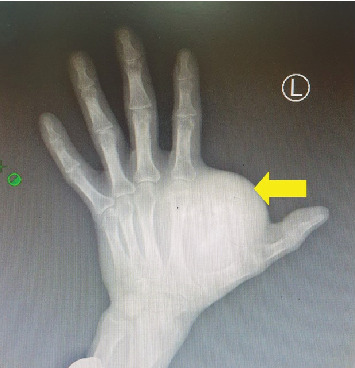

摘要滑膜肉瘤是一种罕见的软组织恶性肿瘤,具有明显的转移潜能。虽然它们可以发生在身体的各个部位,但它们最常见于四肢。这些肿瘤通常发生在儿童和年轻人身上,50岁以上的人很少发生。由于其生长缓慢且无痛的性质,滑膜肉瘤常被误认为是良性病变。标准治疗包括完全手术切除阴性切缘,这提供了良好的5年预后。这个病例强调了早期识别和干预治疗软组织肉瘤的重要性。在这个病例报告中,我们报告了一个57岁的非洲男性,他的左手有2年的渐进的,无痛的肿胀史,诊断为滑膜肉瘤。患者通过完全手术切除成功治疗。

Synovial sarcomas are rare malignant soft tissue tumors with significant metastatic potential. Although they can occur in various parts of the body, they are most commonly found on the extremities. These tumors typically develop in children and young adults, making occurrences in individuals over 50 years of age unusual. Due to their slow-growing and nonpainful nature, synovial sarcomas can often be mistaken for benign pathologies. The standard treatment involves complete surgical excision with negative margins, which offers a favorable 5-year prognosis. This case highlights the importance of early recognition and intervention in managing soft tissue sarcomas. In this case report, we present a 57-year-old African male with a 2-year history of gradual, nonpainful swelling on his left hand, diagnosed as synovial sarcoma. The patient was successfully treated with complete surgical excision.